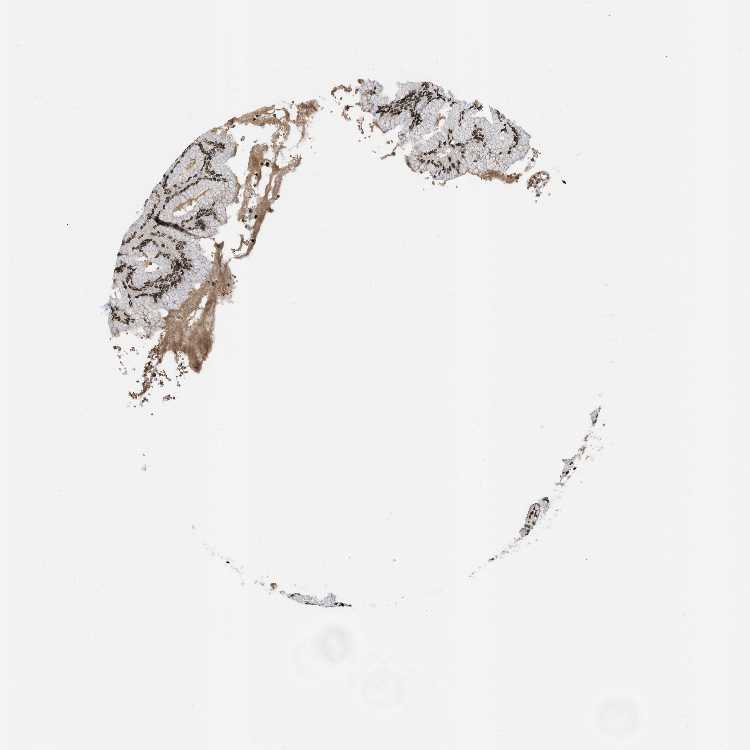

STOMACH 1 - Antibody stainingi

Antibody staining in the annotated cell types in the current human tissue is reported as not detected, low, medium, or high, based on conventional immunohistochemistry profiling in selected tissues. This score is based on the combination of the staining intensity and fraction of stained cells.

Each image is clickable and will lead to virtual microscopy that enables deeper exploration of all samples and also displays staining intensity scores, fraction scores and subcellular localization as well as patient and tissue information for each sample.

Antibody HPA016832Antibody HPA020076Antibody CAB001969

Glandular cells HighHighHigh